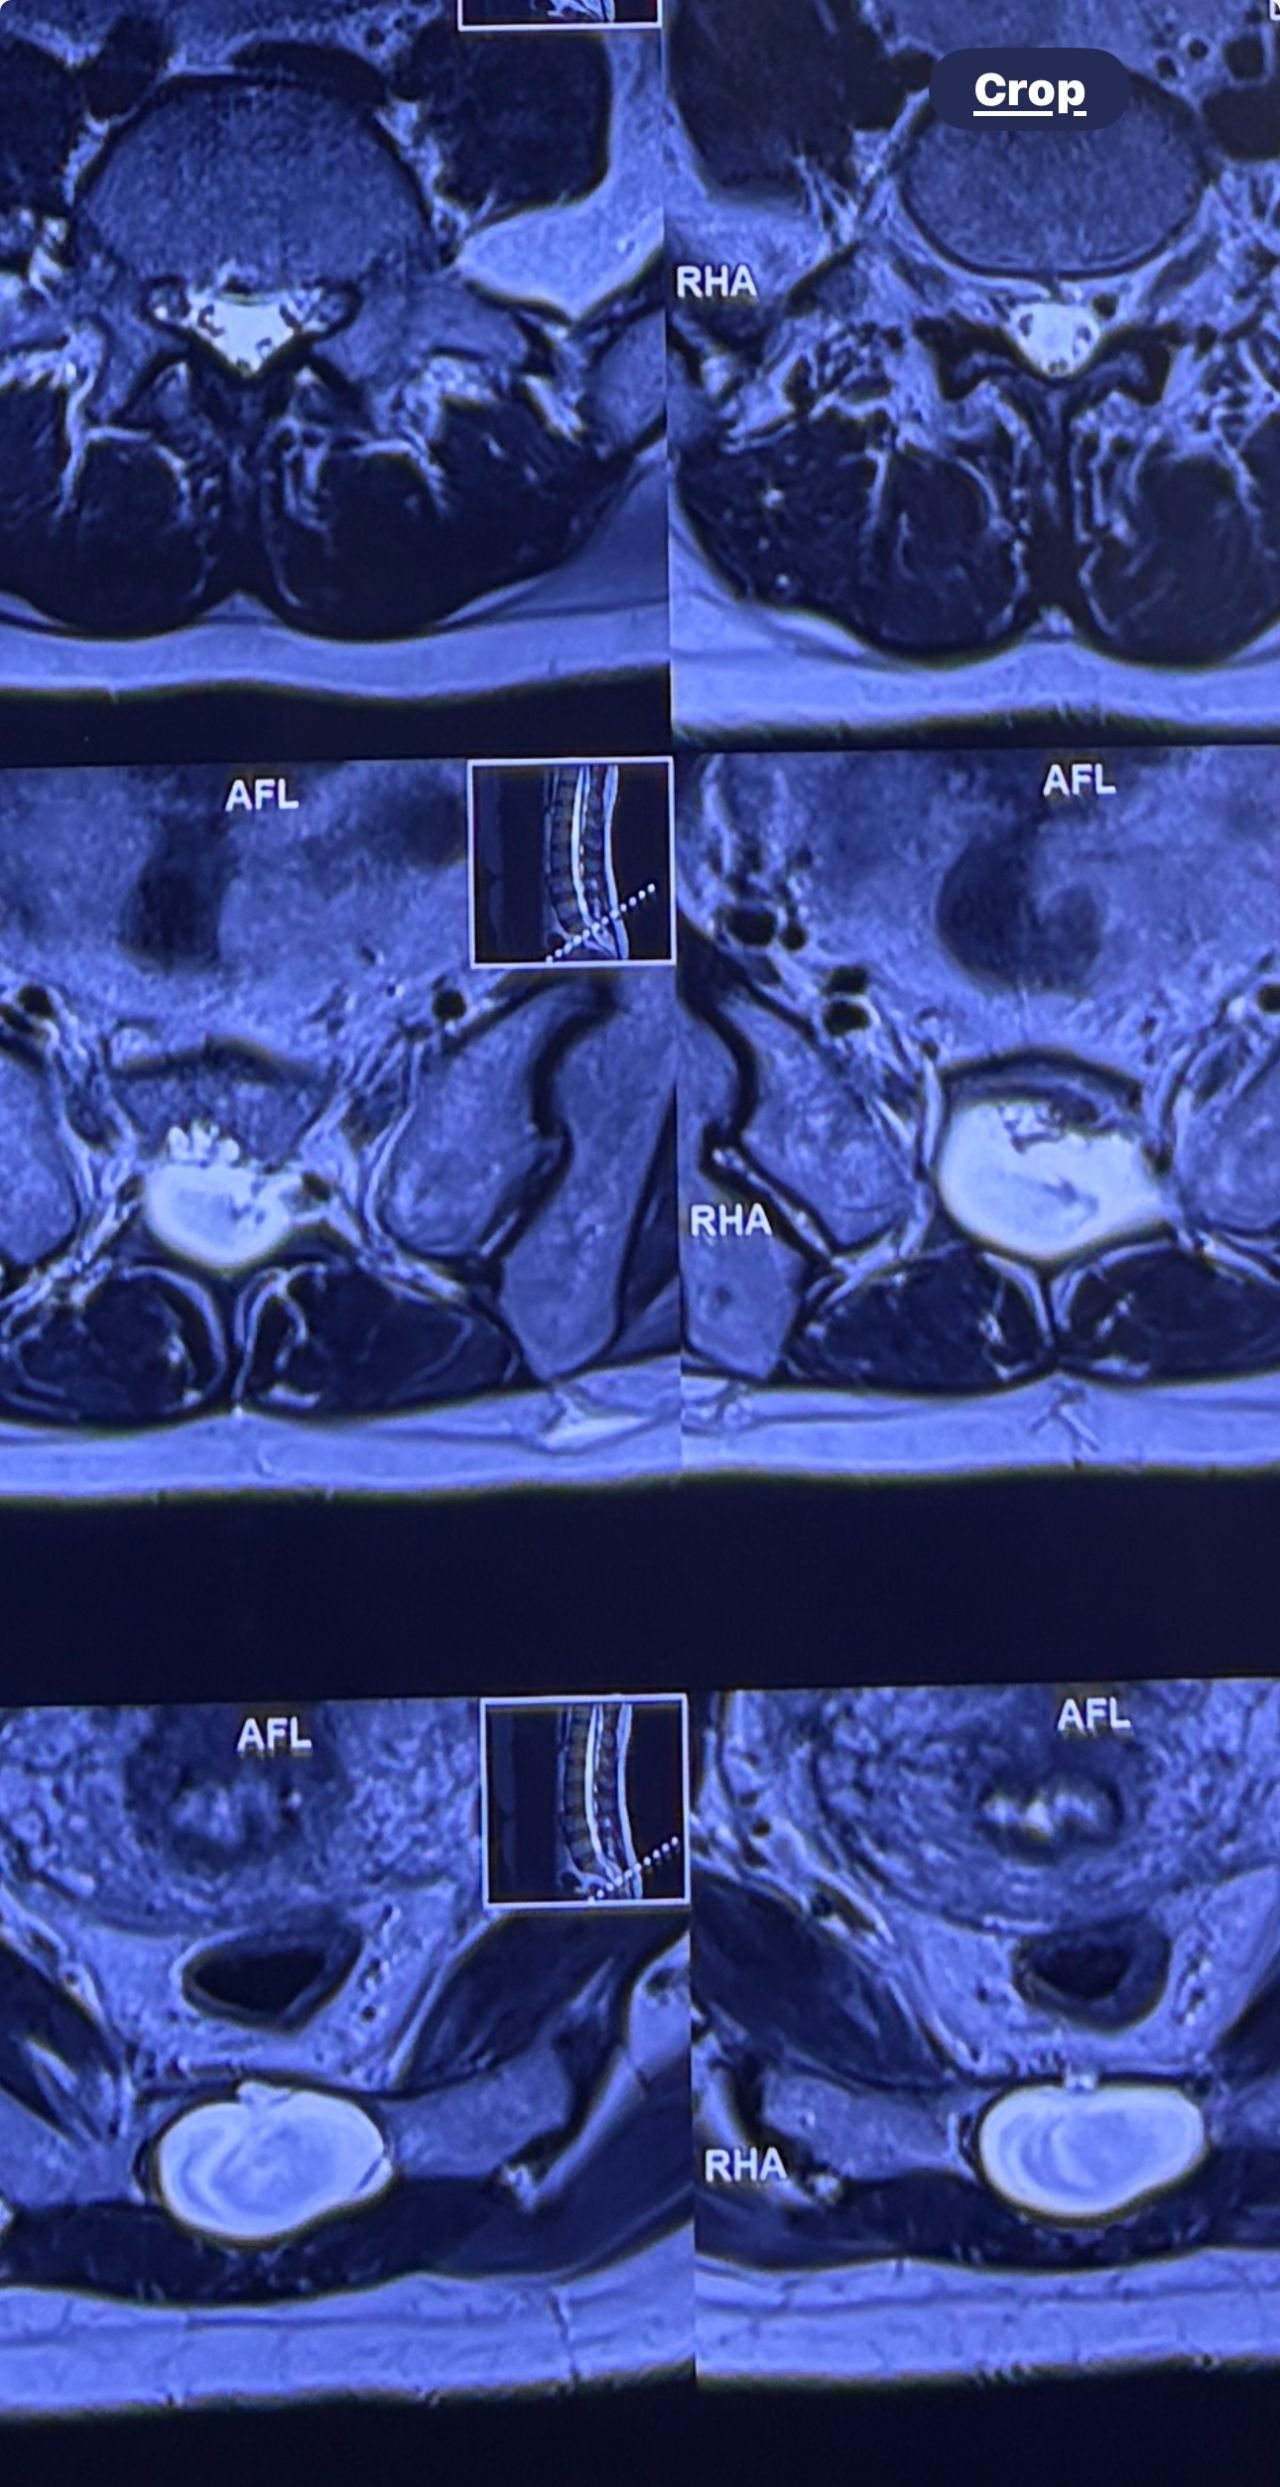

46 years old female patient presented to my clinic yesterday june 1/2025 with LBP and radicular L leg pain for several months which hasn’t responded to physio 2 neurosurgeons have visited her and didn’t suggest any surgery Neurological exam was unremarkable please see her mri/ emg/ncv and her huge tarlov cyst and possible L IVF L4-5 hyperbulge I ordered sacrum mri and ct scan and new emg/ncv and asked her with her sacral Ct scan and MRI first sees another two famous neurosurgeons and see if that large cyst is the reason for her pain if not i can work on her L4-S1 area Do you think her radicular pain can originate from her large cyst in sacrum? Do you consider surgery and removing her sacral cyst?